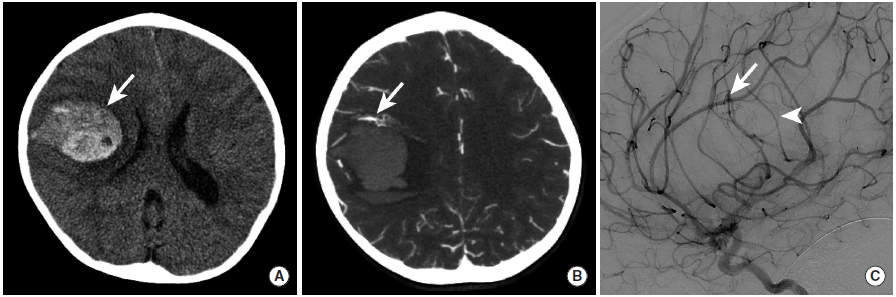

图13

本例为一名儿童患者的影像学检查,由于小脑动静脉畸形破裂引起脑实质内出血。

图A:CT平扫显示右额叶高密度影,提示脑实质内出血(长尾箭头)。

图B:CTA的MIP图像显示沿着出血灶的前缘可见的血管缠结(长尾箭头)。

图C:DSA检查确定了动静脉畸形的存在(长尾箭头),并且可见一细小的早期引流皮层静脉影(三角箭头)。